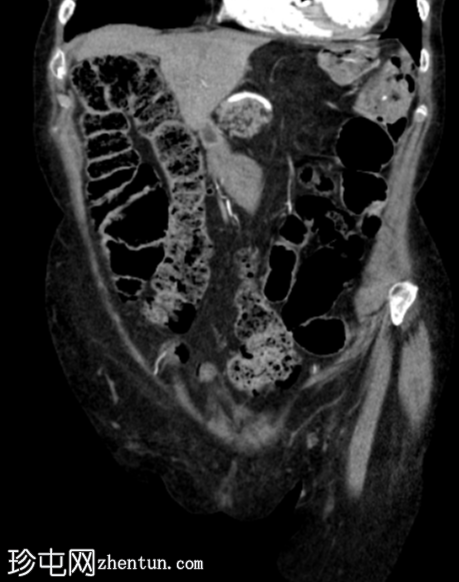

5.png

冠状位

平扫

平扫图像显示左侧结肠脾曲处可见小憩室,伴结肠周围脂肪间隙条索状改变,提示急性结肠憩室炎。

动脉早期可见造影剂外渗,冠状位和矢状位最大强度投影(MIP)图像也可见,位于憩室炎同一部位,符合活动性出血表现。